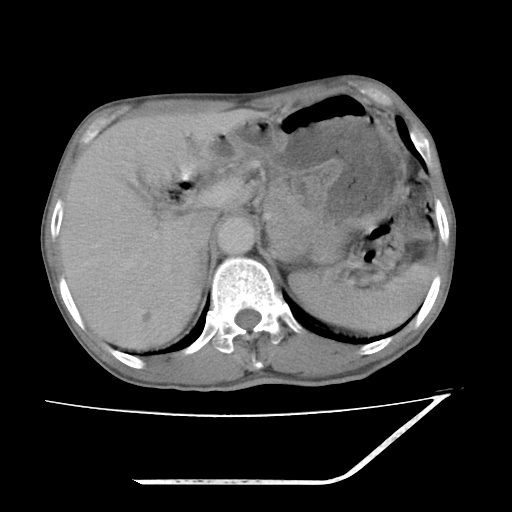

增强

考虑右肾盂癌,肾动脉受侵,右肾功能减退,右肾盂输尿管积水,管壁增厚,考虑种植转移,应该把下面扫完的

支持右侧肾盂癌伴肾静脉瘤栓形成可能性大,右肾结石.肝右叶后段低密度影,不除外转移.

右肾盂旁ca并肾静脉瘤栓形成/肾功能降低。

右肾结石。

支持 右侧肾盂癌伴肾静脉瘤栓形成可能性大,右肾结石;肝右叶后段低密度影,不除外转移。

1.右侧肾盂癌伴肾盂积水。

2.肾脏功能减退,原因有:(1)肾动脉受侵。(2)肾静脉受侵(3)肾积水,等。本例,肾动脉显影较好,但受压明显;肾静脉无明显显示,受压或静脉癌栓,下腔静脉腔内未见明显充盈缺损。